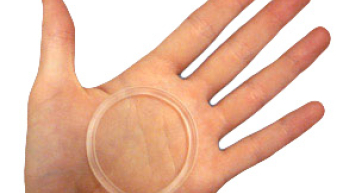

Com a evolução da medicina e a preocupação em facilitar cada vez mais a vida das mulheres e também...